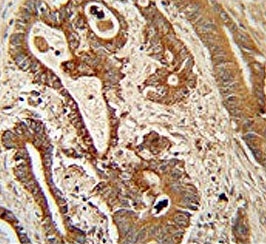

IHC testing of FFPE human colon carcinoma tissue with ETHE1 antibody. HIER: steam section in pH6 citrate buffer for 20 min and allow to cool prior to staining.